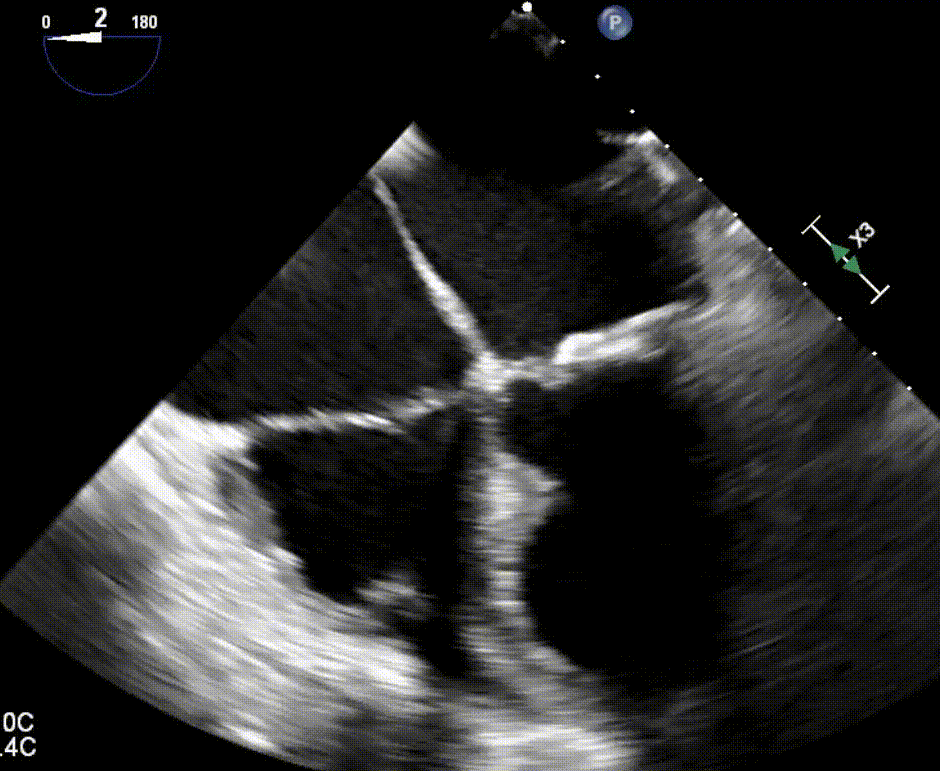

TEE preview: severely depressed LV and RV function

Severe biventricular dysfunction. Interpret the finding, prioritize immediate concerns, and outline your anesthetic management.

Transesophageal Echocardiography (TEE)

Demonstrate your diagnostic expertise with our interactive TEE station. Review high-quality echocardiogram loops—such as right and left ventricular assessments—while simultaneously tracking patient vitals. Accurately interpret complex hemodynamic states exactly as expected in the live exam.

OSCE — TEE (combined station)